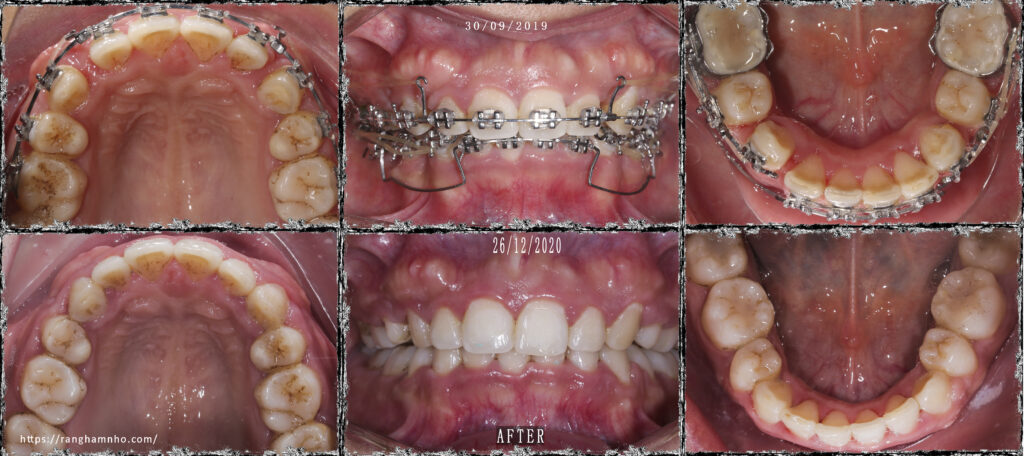

iBệnh nhân này đã được điều trị 2 năm tại một cơ sở phòng khám nha khoa khác. Bệnh nhân hô cả răng và xương & cười hở lợi. Tình trạng niềng hỏng rất nghiêm trọng, khớp cắn sâu 100%, mặt hô nhiều chưa được cải thiện.

Bệnh nhân được giải quyết khớp cắn sâu bằng cung tiện ích UA trên dây TMA 17×25. Kết quả không được hoàn hảo, nhưng là chấp nhận được đối với 1 case niềng hỏng đã quá thời gian điều trị rất lâu.